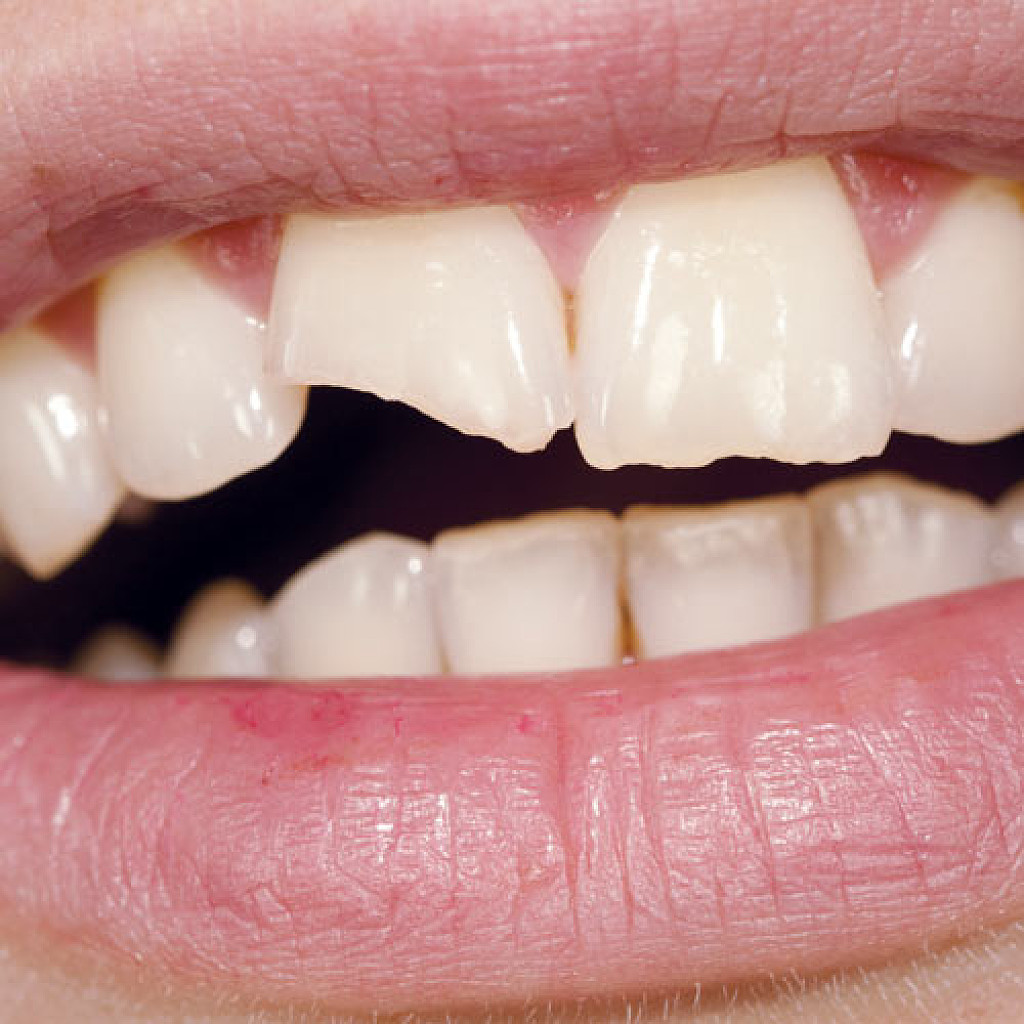

4 Longitudinal Fracture Issues And How They're Treated

Cracked teeth can happen due to a variety of circumstances: trauma due to an accident, chewing on hard food, a weak tooth structure. Sometimes, those cracks result in a type of damage called longitudinal fractures. While these fractures don’t always cause symptoms, they can cause pain and grow bacteria, which can lead to irritation and infection. Luckily, dental professionals can treat longitudinal tooth fractures, and the process to recovery will depend on the type of fracture. Here are the four types to be aware of.

Types of Longitudinal Fractures

1. Craze lines: While craze lines are considered a fracture, they’re not considered a dental emergency and generally do not need treatment. That’s because these lines only affect the tooth enamel and do not cause pain. Teeth grinding, nail-biting, or changing temperatures in the mouth may cause these types of fractures. While these cracks should not cause concern, some adults seek out cosmetic fixes like teeth whitening.

2. Fractured Cusp: Fractured cusps occur when a piece of a tooth’s chewing surface breaks off, typically near a filling. This type of fracture usually does affect your pulp or cause pain and typically can be repaired through a filling or crown.